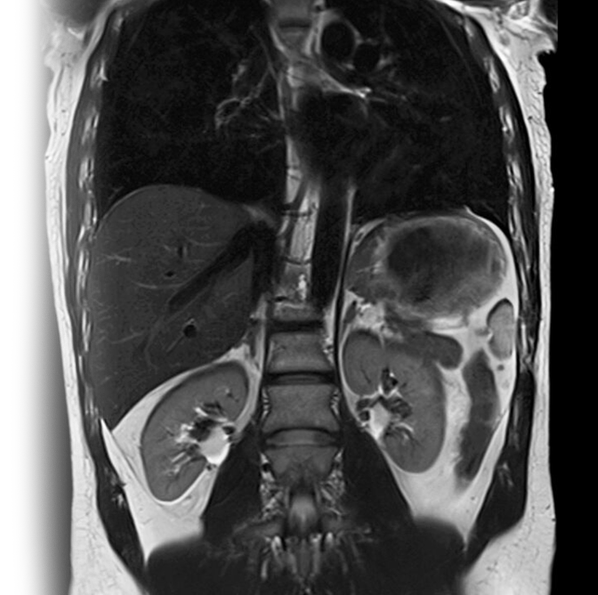

МРТ брюшной полости и забрюшинного пространства с контрастированием